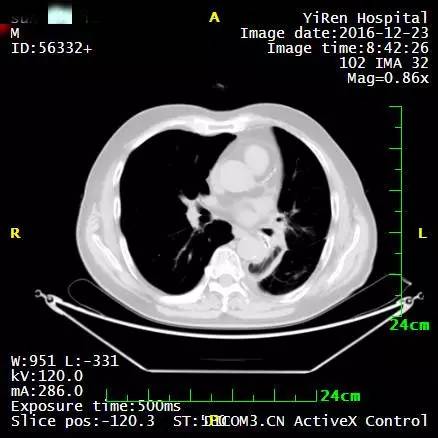

2、患者男性,64岁,小细胞肺癌

2016年3月,王先生因咳嗽加重就诊于当地医院,支气管镜病理检查提示:考虑小细胞癌的可能性大。

化疗一周期,病情无改善症状加重。

2016年4月,王先生接受了A45治疗,一个月后复查,病灶明显缩小,2016年7月复查,病灶进一步缩小,由于A45治疗具有明显的远观效应,能够激发自身的免疫系统,长期有效的消灭体内肿瘤,2016年12月,王先生肺部病灶几乎全部消失。

治疗前

治疗后

治疗后两个月

治疗后7个月

目前王先生状态良好,没有任何复发迹象。